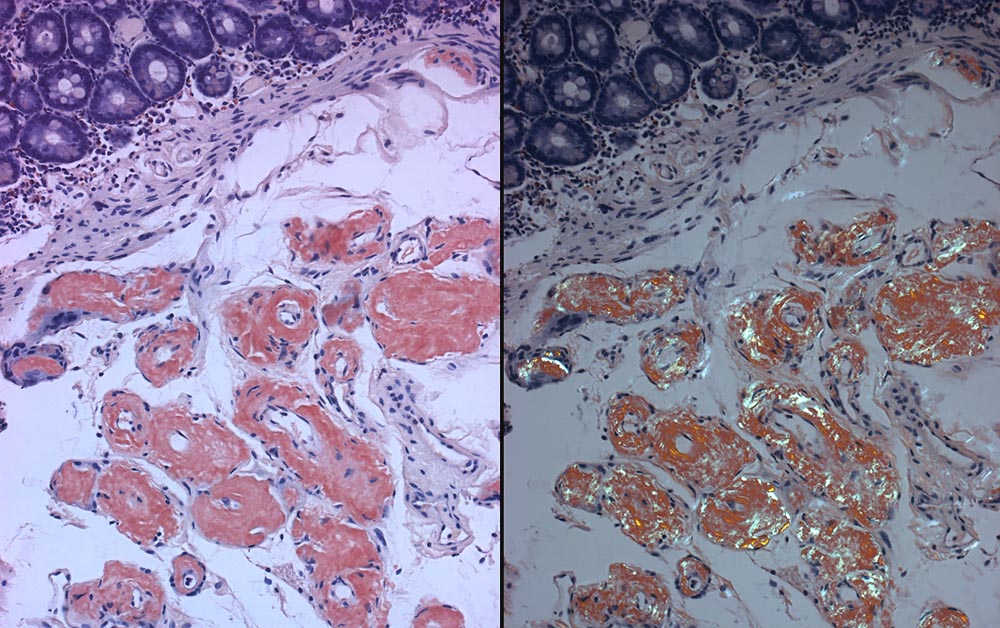

Vaskuläres Typ AL-Amyloid des Duodenums

Azelluläre Amyloidablagerungen in den Gefässwänden der Submukosa der Duodenalschleimhaut. Flaschengrüne Doppelbrechung der Amyloidablagerungen (rechts).

Multiples Myelom. Bekannte AL-Amyloidose vom Typ Lambda Leichtketten.